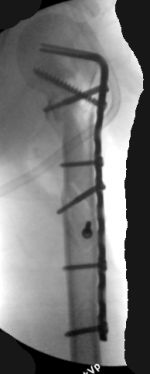

Although we can not see exactly the head piece, and assuming that there are not signs of infection, my suggestion would be to do some type of "bridging" procedure : implant fixation in head piece and distal main fragment, and the rest to be left on its soft tissue attachments (living bone graft).

I just did this attached case, using 90 degrees angled blade plate, and this would be my preference in all similar cases.

Two days ago, I had to plate TWO humeral NONUNIONS after intramedullary nailing. Just to remove them from proximal end, significant damage had to be done to the rotator cuff. My belief is (and supported by the most of recent literature) is that the plating is a better option for humeral fractures.

Good luck and send us your postoperative images, please. Sincerely,

Отправитель: Alexander Chelnokov 05 Октябрь 2003, 13:41

EKTE> I just did this attached case, using 90 degrees angled blade plate, and

EKTE> this would be my preference in all similar cases.

We don't even have so long plates in stock...